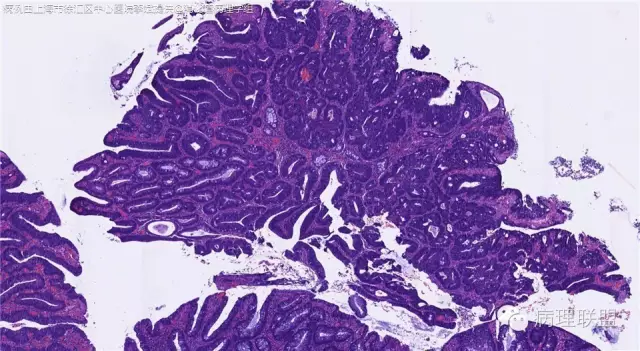

男,72岁,距肛门口30cm息肉。大体:灰白结节1.5*1*0.8cm拟发管状腺瘤并部分区高级别,请各位老师指导!(病例由上海市徐汇区中心医院 李斌 提供,致谢!)

这一例有两种不同看法,按WHO标准,为高级别,按实际工作,要发粘膜内癌。WHO第三版与第四版均提出,侵犯至粘膜下层才能诊断为癌,声称结直肠粘膜内没有淋巴管,发生转移的概率较小,但是粘膜内有血管,肿瘤侵出粘膜腺体基膜以外,就能侵犯血管,照样可以发生血道转移。文献报告与我们的工作实践,发现腺瘤、高级别(没有侵出基膜)的患者,同样有发生血道转移。因此,我们废弃了这一条WHO标准(不是所有的WHO标准都是一定要执行的)。只要异型增生腺体呈毛刺状、迷芽状侵出粘膜腺体基膜,位于粘膜肌层以内,就发粘膜内癌。

@李斌 结肠腺瘤这例我认为已经有黏膜下浸润了,因为有些腺体间的间质已经不是固有膜间质而是促结缔组织增生反应的间质了。但即使有浸润癌,如果息肉完整摘除、癌成分分化好、没有脉管瘤栓、浸润癌距切缘大于1mm(日本标准还要看浸润癌超出黏膜肌深度和肿瘤出芽情况),也不需要进一步治疗。所以,对于这类可能存在争议的病变,特别是息肉已经完整切除的病例,诊断的关注点就应该放在寻找需不需要进一步治疗的证据上了。@邓永键 2010版WHO在腺瘤部分的陈述中已经写出对于有局灶浸润性生长的病例也可以称黏膜内癌,他们在悄悄的让步。